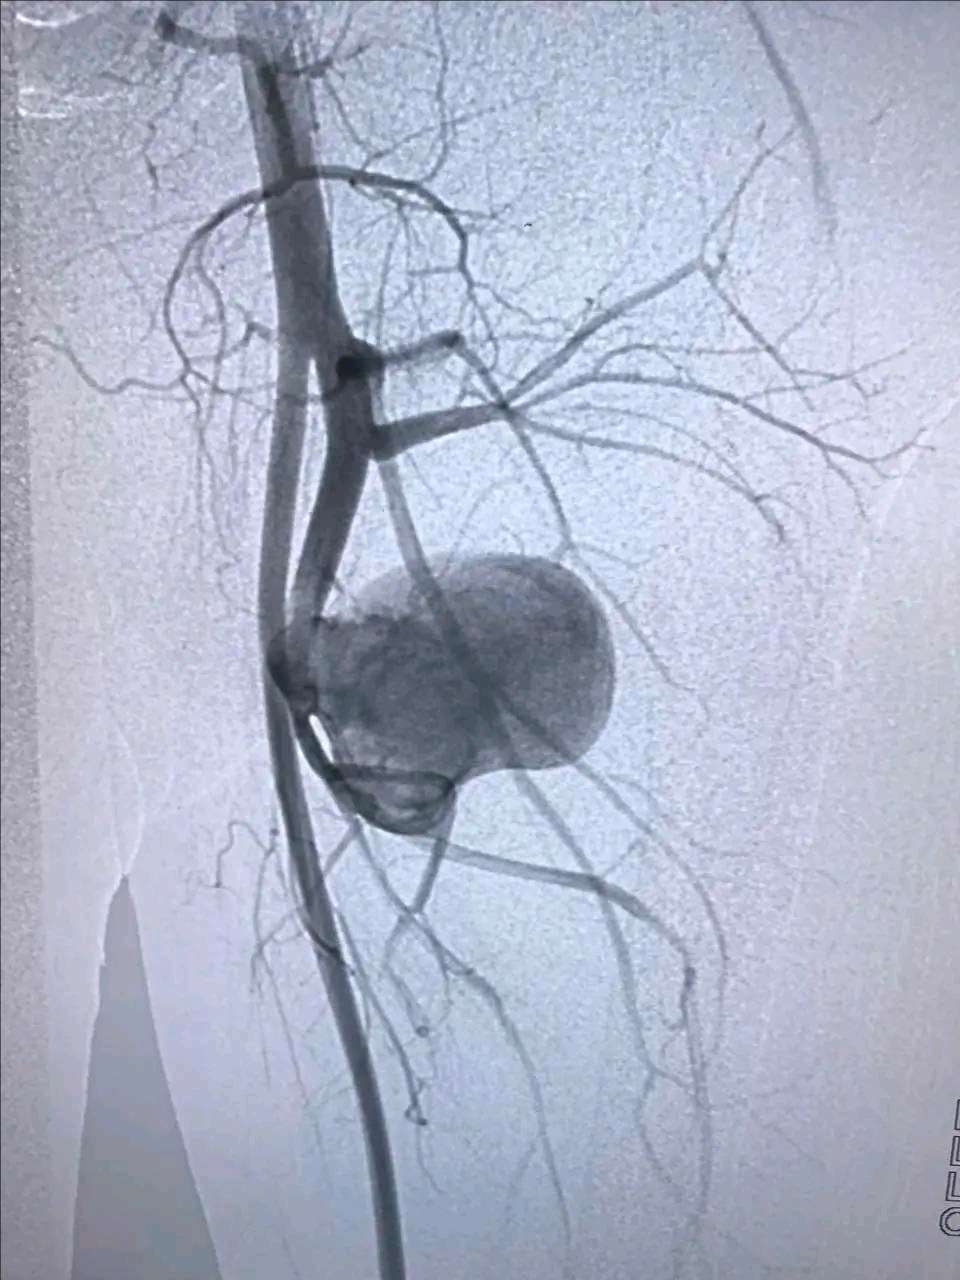

DSA造影检查